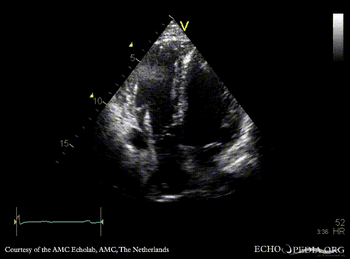

ARVD

Courtesy of: AMC Echolab, AMC, The Netherlands

PLAX: right ventricle dilatation in patient with ARVD PSAX: dilated right ventricle